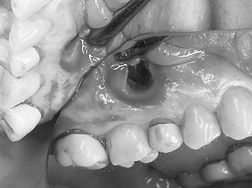

探針をつかい腫脹部から骨の欠損範囲を確認する。

縫合時の粘膜断端が骨面になるよう欠損辺縁より広めに切開線を設ける。

目視できるよう開放された骨欠損部